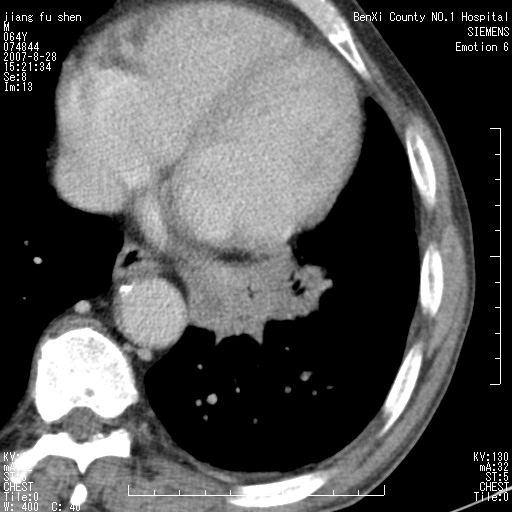

男、64、咳嗽、发烧一周、左肺呼吸音稍弱。既往肺结核,右手结核。

本次扫描患者未带原片,左肺下叶发现病灶。左肺上叶空洞,5组淋巴结肿大,1cm左右。

病灶边缘可见多量较长棘影及纤维条索状影,除外病灶边缘较光整,病灶有分叶表现,但多表现为较浅分叶,且向周围伸出之叶多呈尖角改变,且边缘较光整,病灶增强呈中度延时增强,且早期及中期仅轻度增强,结合患者病史,多考虑继发型肺结核,炎性增殖灶形成,不除外肺癌

左下叶支气管变窄,管腔光滑。软组织形状不规侧,分叶呈角形。结合病史考虑结核可能性大。肺癌不除。